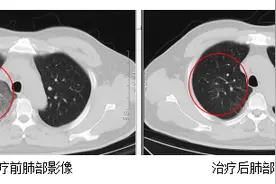

合肥市民王先生喜欢户外运动,一个月前在无明显诱因下反复高热、剧烈头痛,体温最高达38摄氏度。王先生一开始以为这只是普通的细菌感染,想自己在家吃点消炎药来治疗,但是由于有发热症状,王先生来到离家较近的发热门诊就诊,排除新型冠状病毒肺炎后,通过初期相关检查,医生考虑王先生是肺部感染,予以头孢、左氧等抗感染及抗病毒治疗后,体温不降反升,最高达40摄氏度,此时,他还出现了咳嗽、胸闷、气喘等不适症状。